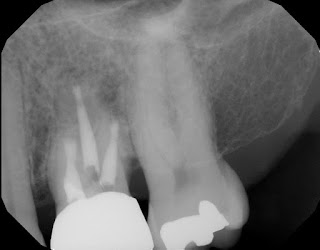

1 year recall. Patient fully functional and asymptomatic.  Radiographic healing evident.